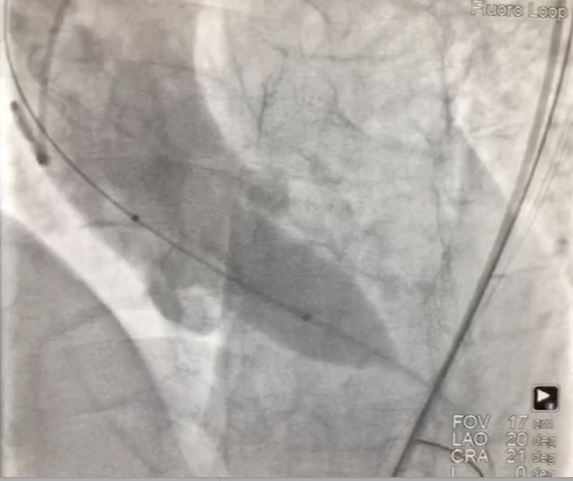

1、经右股动脉将Emboshield Nav6放栓塞装置输送至左、右颈内动脉。

2、经左股动脉入路,顺利跨瓣后,选取20 mm球囊于180 bpm下快速起搏预扩,显示无漏,左、右冠脉未受影响,但可见左冠窦、无冠窦巨大钙化团块。

主动脉根部造影示瓣膜位置合适(深度2 mm),轻度瓣周漏。遂释放瓣膜,撤回脑?;ぷ爸茫质踉猜晒?。